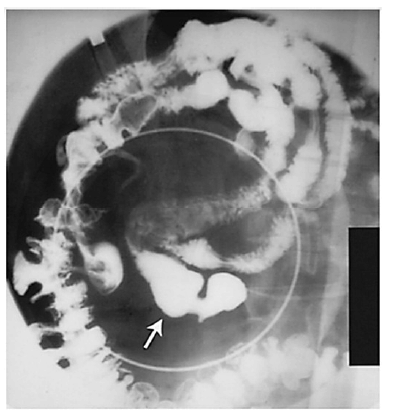

Um paciente do sexo masculino, de 38 anos de idade, assintomático, chega ao consultório médico de um cirurgião em razão de uma alteração em exame de imagem. O paciente é previamente hígido. Refere praticar atividade física, que consiste em corridas e academia quatro vezes por semana, no total. Nega uso contínuo de medicações, tabagismo, alcoolismo e uso de drogas. Além disso, relata não ter tido alergias medicamentosas nem ter feito cirurgias prévias. Nega dor abdominal, náuseas, vômitos e outros sintomas. Declara não ter ocorrido emagrecimento recente. Ao exame físico, o paciente está em bom estado geral, lúcido e orientado. Os resultados de seus exames são: PA = 120 mmHg x 80 mmHg, FC = 80 bpm, Sat. de 98% em ar ambiente. Abdome: flácido, depressível, indolor. Sem massas palpáveis ou visceromegalias. O exame alterado foi de raios X de abdome com contraste baritado, que está representado na figura.

De acordo com o caso clínico exposto e com os conhecimentos relacionados à imagem, julgue os itens a seguir.

De acordo com a análise do caso clínico e da imagem, a hipótese diagnóstica para o paciente é divertículo de Meckel.